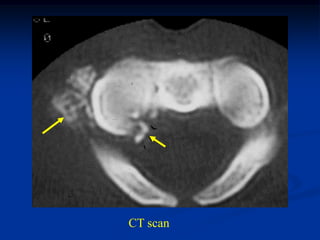

Case #587

42 year male with

combined periosteal

chondroma and

enchondroma next to

each other in femur

Axial CT scan at level of enchondroma

periosteal

chondroma

enchondroma

CT scan